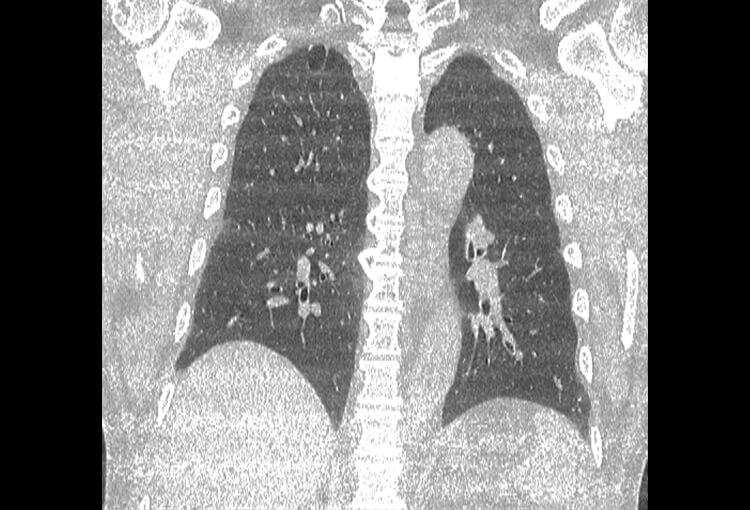

120 kV / 20 mAs / 1 mm

Before FBP (Noise 189) VS After ClariCT.AI (Noise 46) 76% Denoising